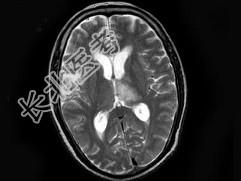

- 单项选择题男,70岁, 头痛,嗜睡伴癫痫发作2次, 行MRI平扫及增强扫描见颅内多发病灶,曾行放射治疗, 病灶明显缩小(此图为治疗前图),据此最可能的诊断为 ( )

A、颅内转移瘤

B、淋巴瘤

C、胶质瘤

D、血管瘤

E、未见异常